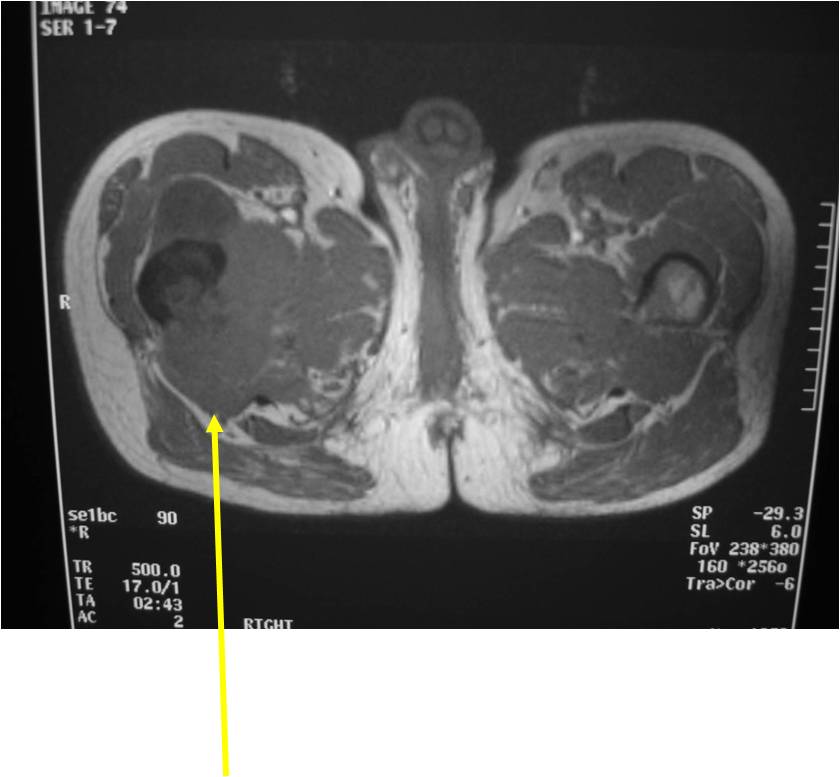

Radiographic Presentation

Radiology emulates pathology: Biphasic Tumor

- One region low grade chondrosarcoma

- Second more aggressive area with bone destruction, lysis of calcification, soft tissue mass

- Cortical permeation and a soft tissue mass in 70% of cases

Ill-defined, lytic intraosseous lesion

- Or extraosseous soft tissue mass

- Devoid of calcifications in continuity with lesions having the features of a cartilaginous tumor

Characteristically abrupt transition between chondroid tumor and dedifferentiated, lytic component

Bone may be expanded and adjacent cortex thickened

(Right Arrow)Aggressive Lytic Area (Dedifferentiated Sarcomatous Component) Cortical Destruction Soft Tissue Mass without Calcification

Biological Behavior

- Very aggressive locally

- Frequently cortical perforation

- Mass is usually large if extraosseous extension occurs